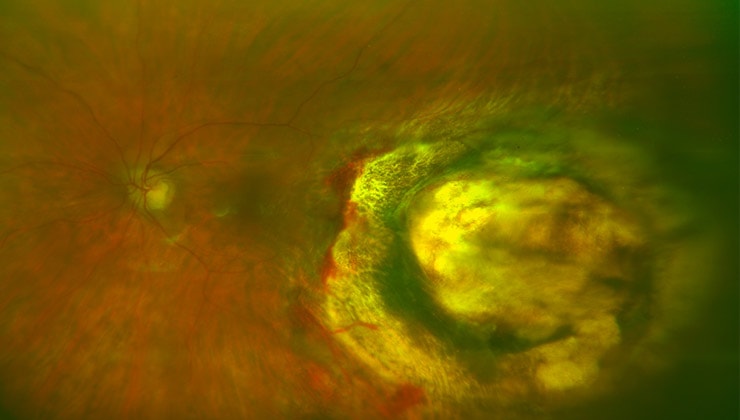

La resección tumoral es la extracción del tumor a través de pequeñas incisiones. Se realiza mediante vitrectomía.

Esta técnica está normalmente indicada para tumores localizados cerca del nervio óptico pero también se puede aplicar en otro tipo de tumores.

Es una intervención que se suele realizar mediante cirugía ambulatoria (excepto a niños a los cuales se suele aplicar anestesia general). Consiste en extirpar el tumor y siempre se aplica adicionalmente radioterapia local para asegurar que no quede ninguna célula tumoral en la zona. Adicionalmente, se aplica aceite de silicona para aplicar la retina y evitar que esta se desprenda.

Los tumores del ojo pueden producirse sobre cualquier tejido, pero el más frecuente, en el adulto, es el melanoma de coroides, un tumor maligno que puede tratarse mediante radioterapia y otros tratamientos con notable éxito. Otros tejidos en los que también pueden aparecer tumores malignos son la conjuntiva, la glándula lagrimal, o la órbita, entre otros. También existen tumores benignos, que normalmente se resecan con facilidad. En el niño, hay un tumor especialmente conocido de la retina, llamado retinoblastoma, que da una apariencia de la pupila blanca y que tiene que tratarse lo antes posible porque puede llevar a la muerte del niño, si no se realiza un tratamiento apropiado.